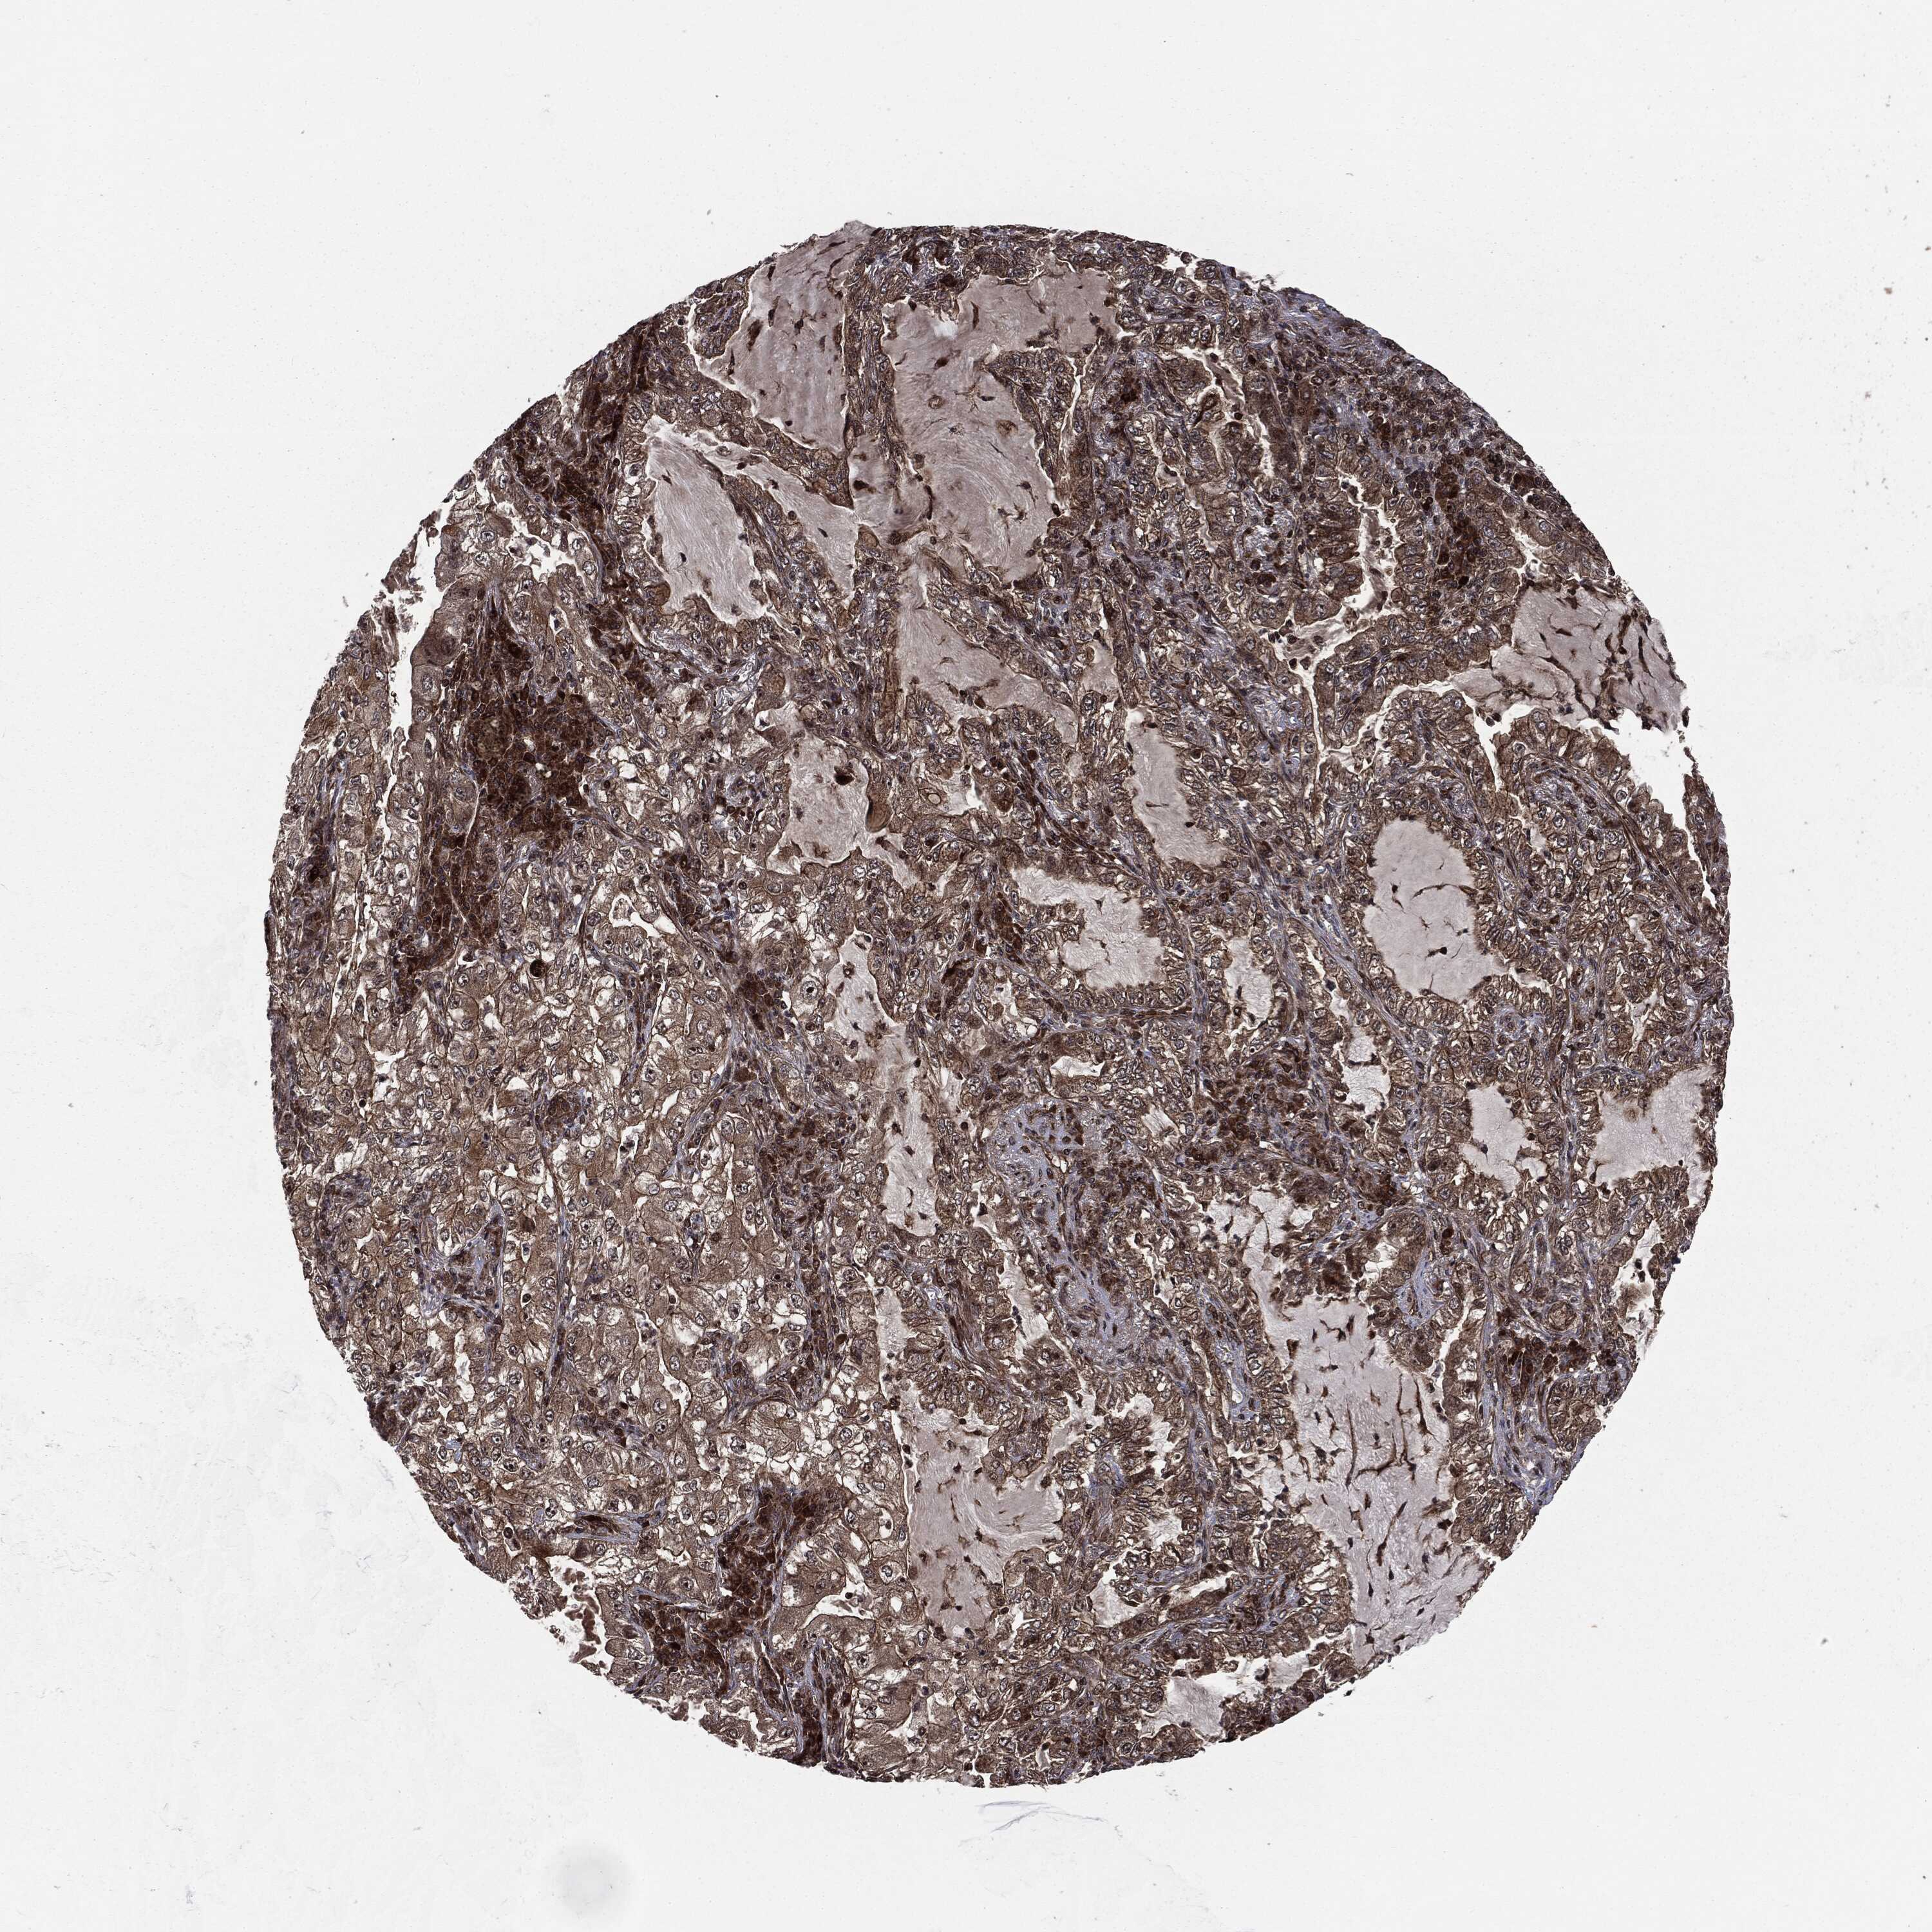

LUNG SQUAMOUS CELL CARCINOMA (TCGA) - Interactive survival scatter ploti

The Survival Scatter plot shows the clinical status (i.e. dead or alive) for all individuals in the patient cohort, based on the same data that underlies the corresponding Kaplan-Meier plots. Patients that are alive at last time for follow-up are shown in blue and patients who have died during the study are shown in red.

The x-axis shows the expression levels (FPKM) of the investigated gene in the tumor tissue at the time of diagnosis. The y-axis shows the follow-up time after diagnosis (years). Both axes are complimented with kernel density curves demonstrating the data density over the axes. The top density plot shows the expression levels (FPKM) distribution among dead (red) and alive patients (blue). The right density plot shows the data density of the survived years of dead patients with high and low expression levels respectively, stratified using the cutoff indicated by the vertical dashed line through the Survival Scatter plot. This cutoff is automatically defined based on the FPKM cutoff that minimizes the p-score. The cutoff can be changed by dragging the vertical line or by entering a cutoff value in the square labeled "Current cut-off".

Under the Survival Scatter plot the p-score landscape (black curve; left axis) is shown together with dead median separation (red curve; right axis). Dead median separation is the difference in median mRNA expression between patients who have died with high and low expression, respectively. It is calculated as follows: median FPKM expression of dead patients with high expression - median FPKM expression of dead patients with low expression. This is intended to aid the user in visually exploring custom cutoffs and the associated p-scores and dead median separation.

Individual patient data is displayed and can be filtered by clicking on one or more of the category buttons on the top of the page. Categories describing expression level and patient information include: high, low, alive, dead, female, male and tumor stages. The scale of the x-axis can be toggled between linear and log-scale by clicking on the "x log" button. Mouse-over function shows TCGA ID, patient information and mRNA expression (FPKM) for each patient.

& Survival analysisi

Kaplan-Meier plots summarize results from analysis of correlation between mRNA expression level and patient survival. Patients were divided based on level of expression into one of the two groups "low" (under cut off) or "high" (over cut off). X-axis shows time for survival (years) and y-axis shows the probability of survival, where 1.0 corresponds to 100 percent.

CARD6 is not prognostic in Lung Squamous Cell Carcinoma (TCGA)

Best expression cut offi

Based on the FPKM value of each gene, patients were classified into two groups and association between prognosis (survival) and gene expression (FPKM) was examined. The best expression cut-off refers the FPKM value that yields maximal difference with regard to survival between the two groups at the lowest log-rank P-value. Best expression cut-off was selected based on survival analysis .

When clicking on this number, the vertical dashed line indicating cut-off, the interactive survival plot, and the Kaplan-Meier curve will be adjusted to show results based on the best expression cut-off.

: 5.45

Median expressioni

Median expression refers to the median FPKM value calculated based on the gene expression (FPKM) data from all patients in this dataset. When clicking on this number, the vertical dashed line indicating cut-off, the interactive survival plot, and the Kaplan-Meier curve will be adjusted to show results based on the median expression.

: N/A

Median follow up timei

Median follow up time refers to the median time (years) after diagnosis with this type of cancer, based on clinical data from all patients in this dataset.

P scorei

Log-rank P value for Kaplan-Meier plot showing results from analysis of correlation between mRNA expression level and patient survival.

N/A

5-year survival highi

5-year survival for patients with higher expression than the expression cutoff.

For melanoma and glioma, 3-year survival is shown.

5-year survival lowi

5-year survival for patients with lower expression than the expression cutoff.

TCGA RNA samplesi

RNA-seq data is reported as average FPKM (number Fragments Per Kilobase of exon per Million reads), generated by the The Cancer Genome Atlas (TCGA) .

Normal distribution across the dataset is visualized with box plots, shown as median and 25th and 75th percentiles. Points are displayed as outliers if they are above or below 1.5 times the interquartile range. FPKM values of the individual samples are presented next to the box plot.

Average pTPM 6.2

Number of samples 489